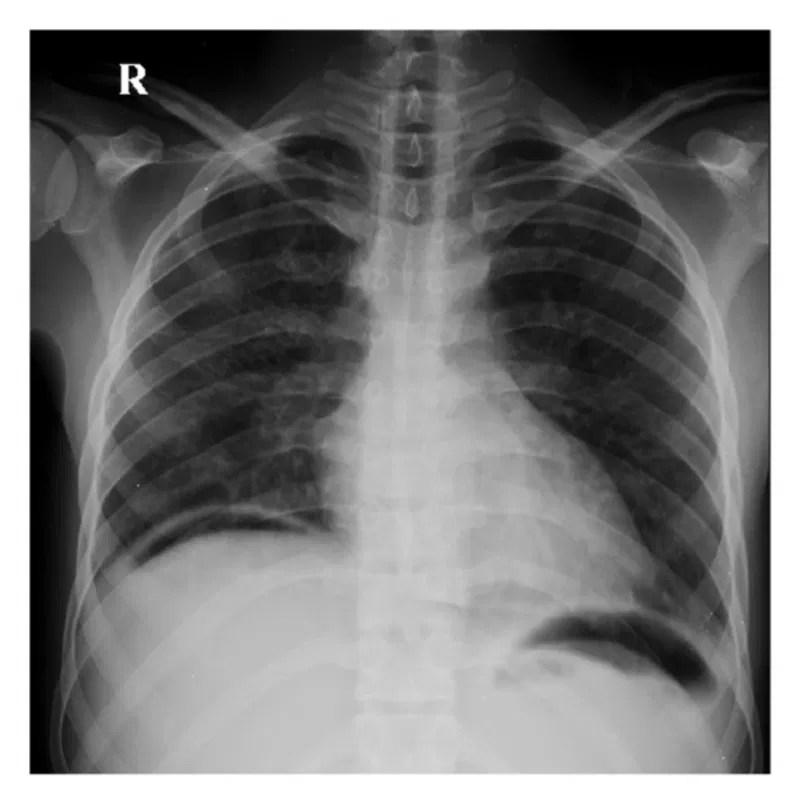

Pneumoperitoneum, usually seen as free air under the diaphragm, is a finding that can be seen on plain abdominal radiographs, signifying a leakage of air, usually from a perforation in the gastrointestinal tract. The diaphragm is a muscle that helps you breathe. This patient had a perforated duodenal ulcer.

Anshu warade free gas under diaphragm. The diaphragm is a sheet of muscle in the chest. This finding usually indicates a rupture of a hollow viscus organ (eg, a gastric, appendicular, or diverticular perforation).

We discuss a unique patient who presented with intermittent abdominal pain for 2 years that worsene. In the setting of an upright patient, free air in the peritoneum will reveal itself as crescentic lucency below the diaphragm often because. The presence of air under the diaphragm is a surgical emergency until proven otherwise.

This can mean disruption of the wall of the bowel. Acute abdominal pain with air under the diaphragm is a sign of gastrointestinal perforation and an urgent laparotomy is usually recommended. Breathing exercises can strengthen your diaphragm and keep it working like it should.